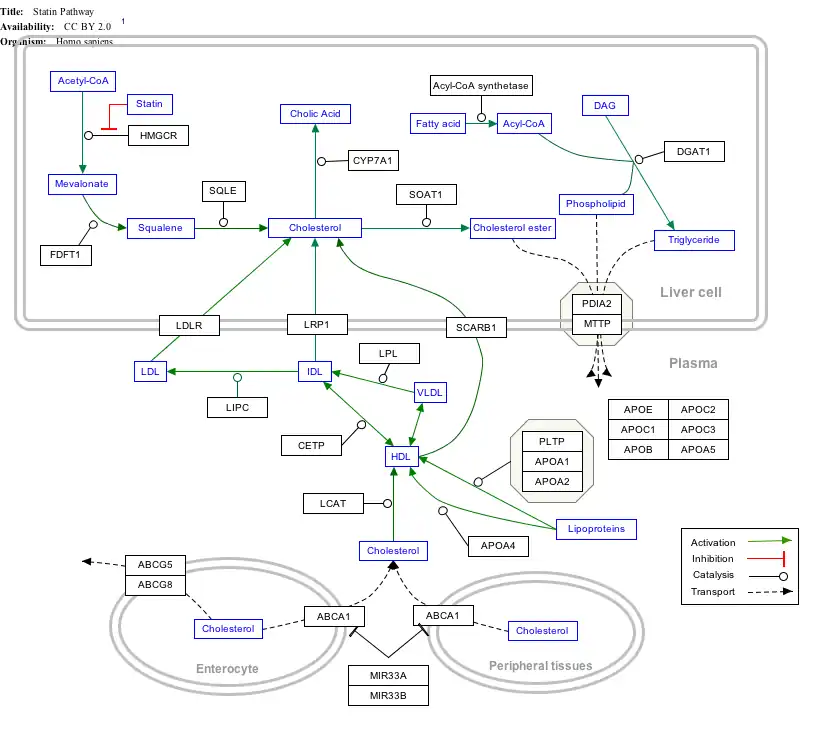

Interactive pathway map

Click on genes, proteins and metabolites below to link to respective articles. [§ 1]

- ↑ The interactive pathway map can be edited at WikiPathways: "Statin_Pathway_WP430".